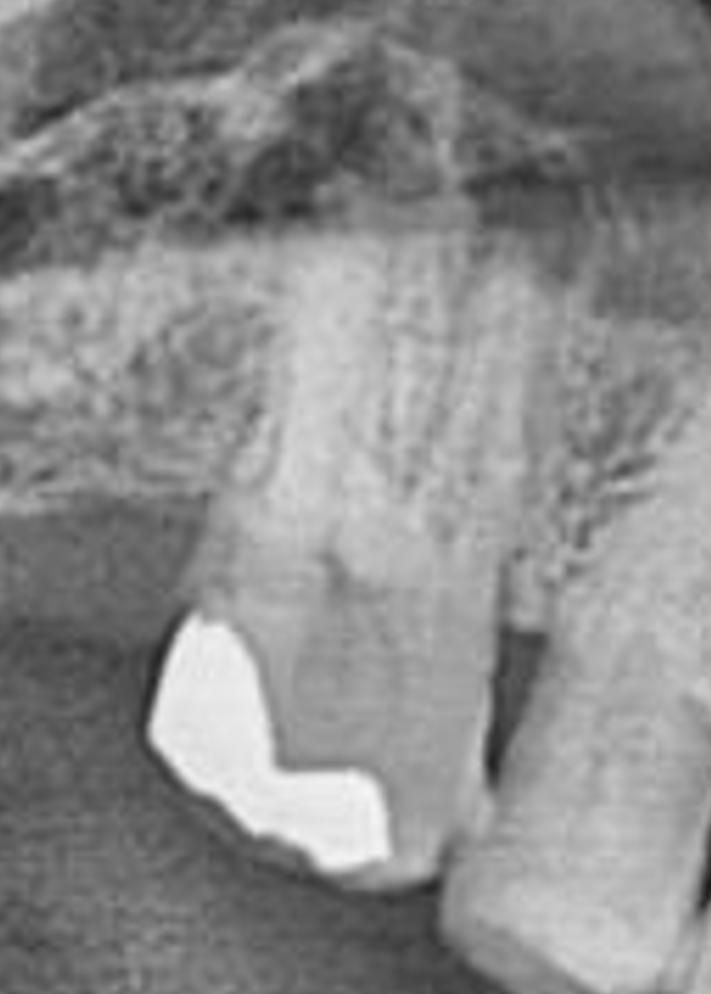

보름전 정도 찍은 엑스레이 사진입니다. 윗쪽 가장 가장자리 어금니입니다. 치주염이나 염증등 이상이 있는지 봐주시기 바랍니다.

사진이 흐려서 명확히 보이지는 않지만 치아의 뒤쪽부분으로 염증이 보이는 것으로 판단됩니다.

엑스레이가 뚜렷하지 않아서 정확히 판단은 어렵지만 치아 뿌리끝에 염증이 있는거 같습니다.

사진으로 봤을 경우에는 치근단 부위에 병소가 보입니다. 치근단의 병소는 치아 내부에 감염 등으로 인해서 염증이 생겼을 때 생기게 됩니다. 치근단에 병소가 생겼을 경우에는 신경 치료를 해야 할 수 있으며 신경 치료를 했을 경우에는 보철 치료가 필요합니다.

자세한 확인을 위해서 치과에서 진료를 받아보는 것을 권유드립니다.

치아 뿌리끝을 근단이라 하고 근단부 염증이 보입니다. 이는 치주에서 비롯된 것일 수도 있고, 치아에서 비롯된 것일 수도 있습니다. 각 원인에 따라 잇몸치료를 할지, 신경치료를 할지 결정합니다. 복합적인 원인일 수도 있고요.